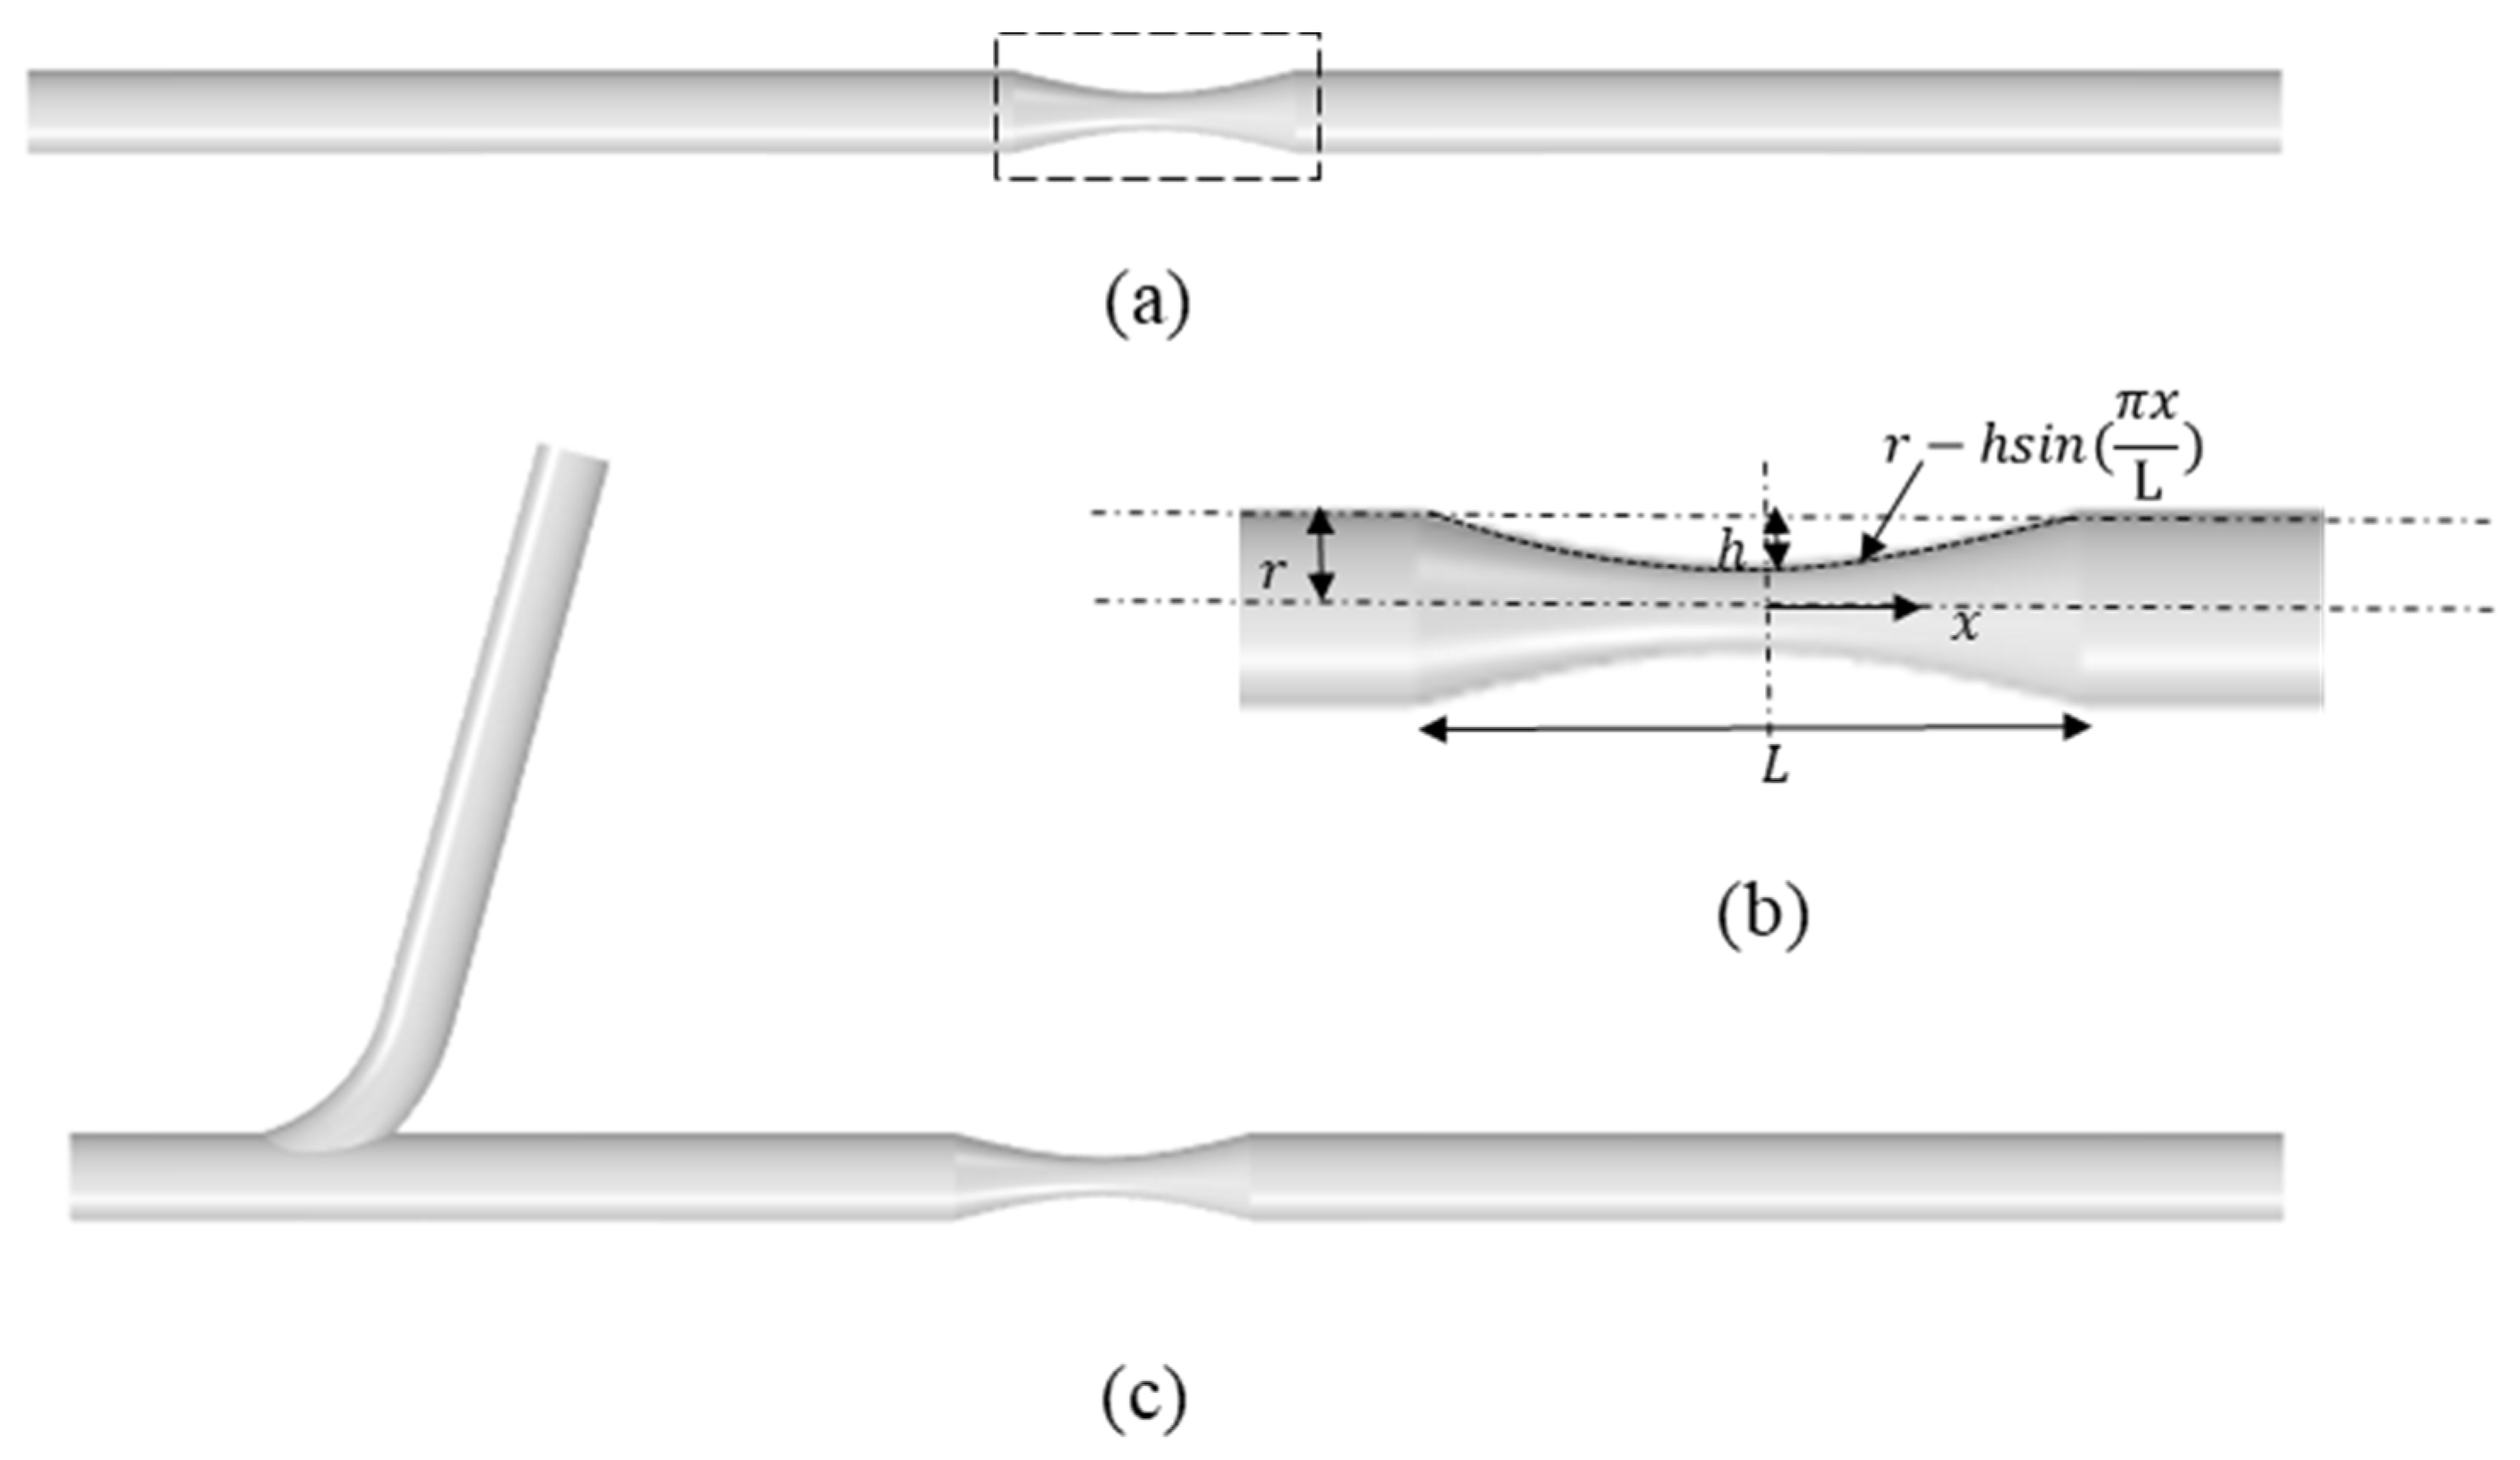

2.1. Idealized Stenosed Coronary Artery Models

3.1. FFR and Flow Distribution in Idealized Artery Models